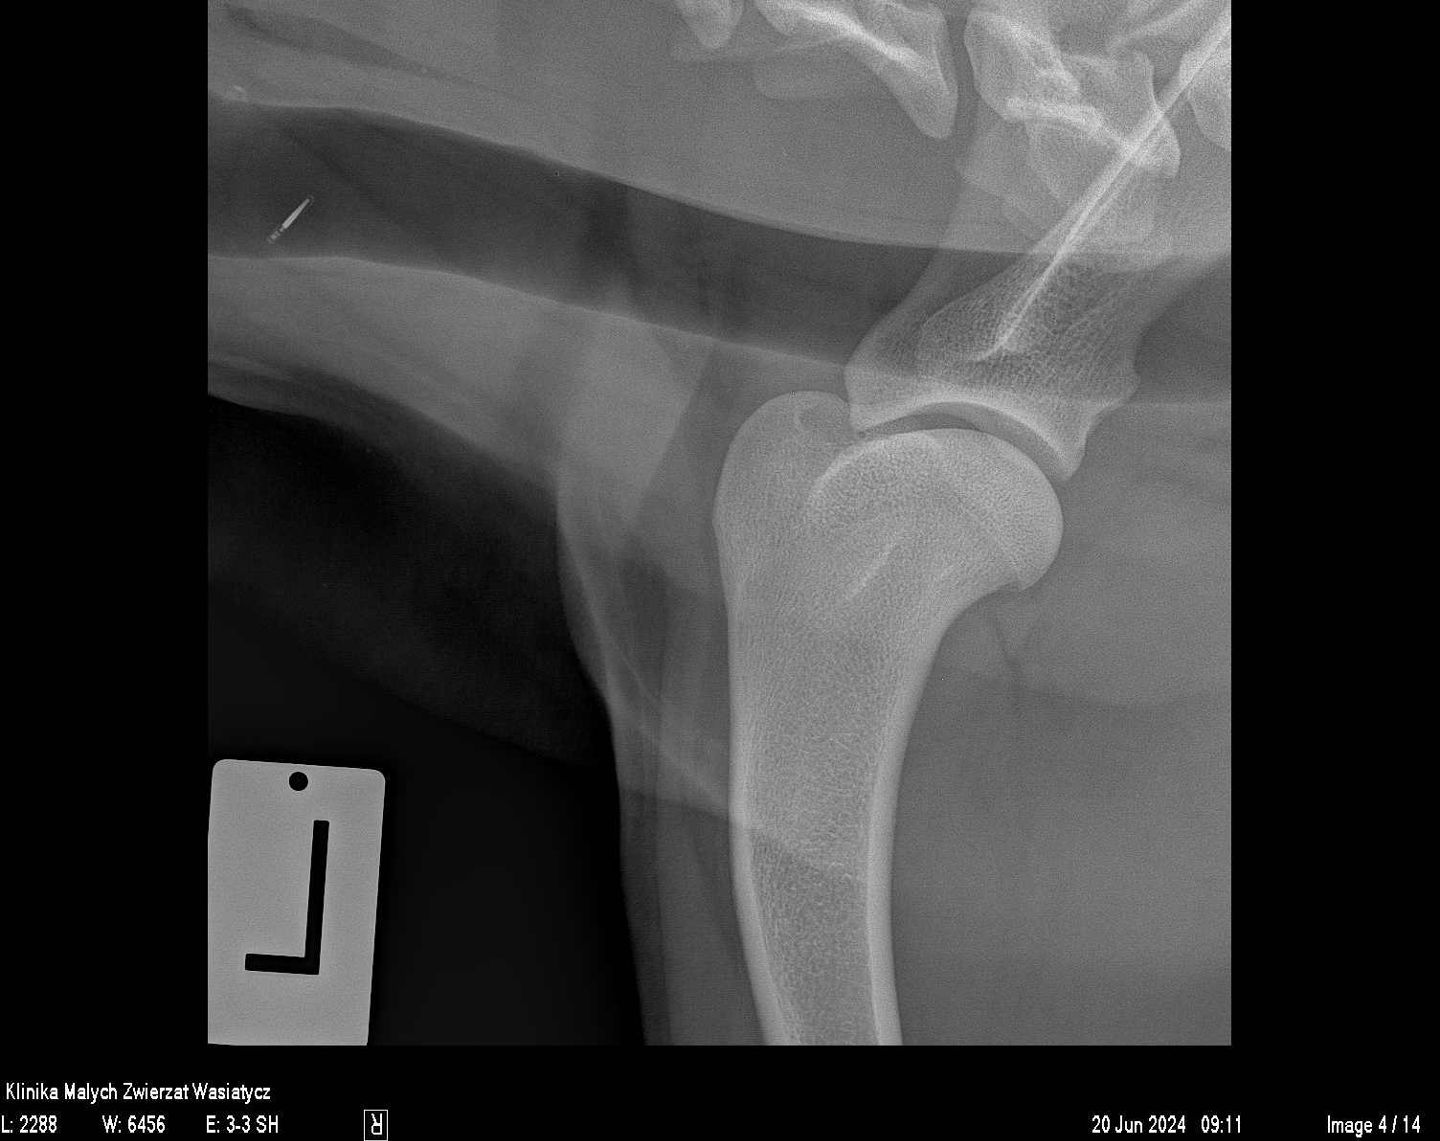

W naszej klinice pracownia rentgenowska stanowiła zawsze bardzo ważne miejsce diagnostyczne. Jako placówka specjalizująca się w ortopedii staramy się zapewnić najwyższą jakość zdjęć rtg, zarówno w zakresie dokładności ułożeń jak i parametrów ekspozycji.

Ponad 20 lat temu, jako pierwsi w polskiej weterynarii, zaczęliśmy wykorzystywać bezpośredni system radiologii cyfrowej, czyli takiej, w której detektor podłączony jest cały czas do komputera. Umożliwia to uzyskanie gotowego obrazu w kilka sekund po ekspozycji i przesłanie go do jednego z gabinetów diagnostycznych chwilę później. Wówczas był to jeden z najlepszych na świecie systemów rentgenowskich niemieckiej firmy Gierth bazujących na detektorach Canon.

Obecnie, w naszej pracy wykorzystujemy najwyższej klasy sprzęt rentgenowski hiszpańskiej firmy Initech, który został specjalnie skonfigurowany zgodnie z naszymi potrzebami. Jest to również system radiologii bezpośredniej.

Rocznie w naszej klinice wykonywanych jest prawie 20 000 zdjęć rentgenowskich. Każde z nich jest wykonywane przez stale doskonalących się specjalistów, analizowane przez wysokiej klasy lekarzy weterynarii, w tym również specjalistów radiologów. Wszystko to sprawia, że badanie rtg dostarcza maksymalną ilość informacji, która potrzebna jest w procesie diagnostycznym.